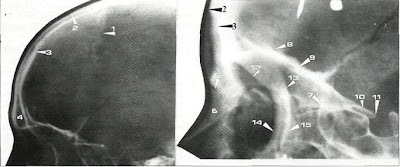

Radiographic anatomy

Radiograph of the lateral view of the frontal bone.

2 external cortical plate of frontal bone

3 internal cortical plate of frontal bone

4 frontal sinus

5 frontonasal suture

6 nasal bone

7 frontosphenoethmoidal suture

8 endocranial surface of frontal bone

9 exocranial surface of frontal bone

10 lesser wing oi sphenoid bone

11 anterior clinoid

12 anterior margin of zygomatic process of frontal bone

13 posterior margin of zygomatic process of frontal bone

14 anterior margin of frontal process of zygomatic bone

15 posterior margin of frontal process of zygomatic bone

Starting from the upper anterior part of the skull at the coronal suture (1), the frontal bone appears as two radio-opaque lines that descend parallel to each other. The outer radio-opaque line represents the external cortical plate of the frontal bone (2), and the inner line represents the internal cortical plate (3), which forms the anterior border of the anterior cranial fossa. These two parallel lines diverge at the forehead area where the frontal sinus(4) appears as a radiolucent area between them. The external cortical plate terminates at the anterior part of the frontonasal suture (5), which appears as a radiolucent line between the frontal and the nasal bones (6). The internal cortical plate extends horizontally and posteriorly, thus terminating at the small radio-opaque triangular area that represents the frontosphenoethmoidal suture (7),

Above the horizontal part of the internal cortical plate there are two radio-opaque lines. The uppermost of these two lines, which appears as a wavy radio-opaque line, represents the endocranial surface of the frontal bone (8), which forms the floor of the anterior cranial fossa. The harmonious radio-opaque curve below the wavy line represents the exocranial surface of the frontal bone (9), which forms the roof of the orbit. This line extends posteriorly to the lesser wings of the sphenoid bone (10) and to the anterior clinoid (11). Anteriorly, it starts at the area of the frontal sinus where the junction of the roof of the orbit and its lateral border can be identified as an angular radio-opaque shadow. The lateral border of the orbit appears as a curved radio-opaque line, which represents the anterior margin of the zygomatic process of the frontal bone (12). At the same area, the posterior margin of the zygomatic process of the frontal bone (13) can be identified as a radio-opaque line descending parallel behind the lateral border of the orbit. These two lines merge with the radio-opaque lines of the anterior and posterior margins of the frontal process of the zygomatic bone (14, 15).